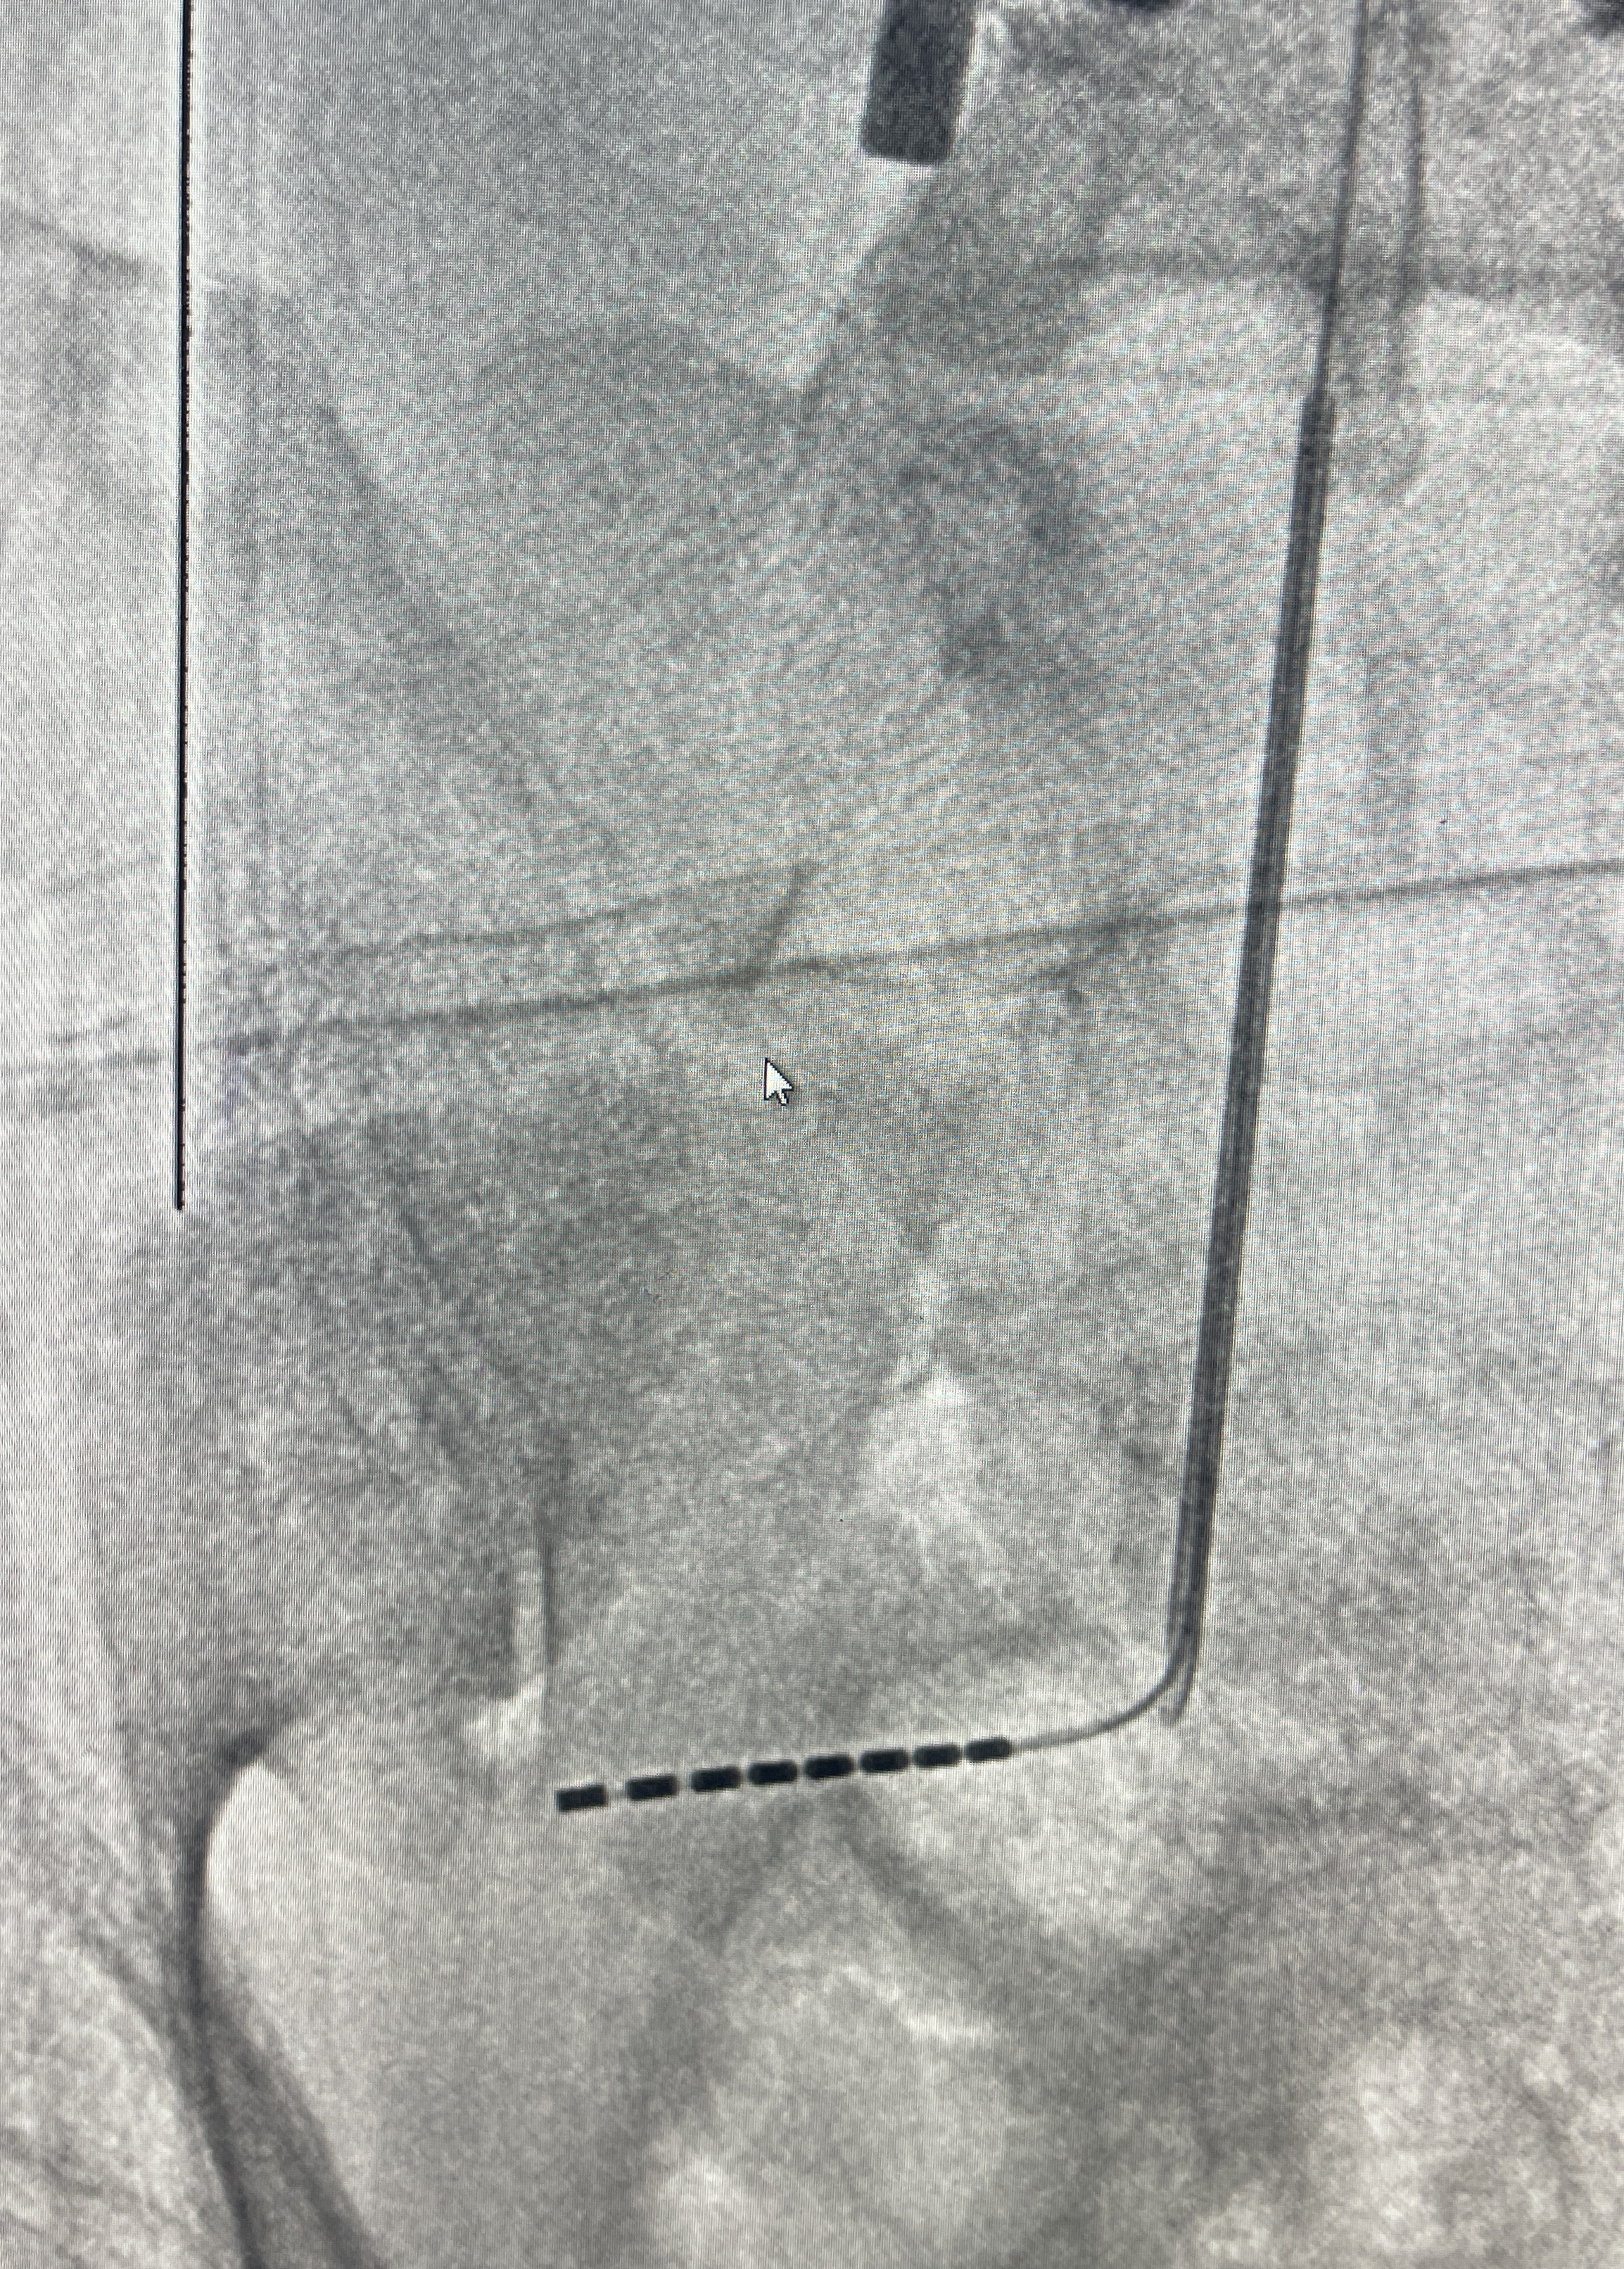

骶神经电极位置